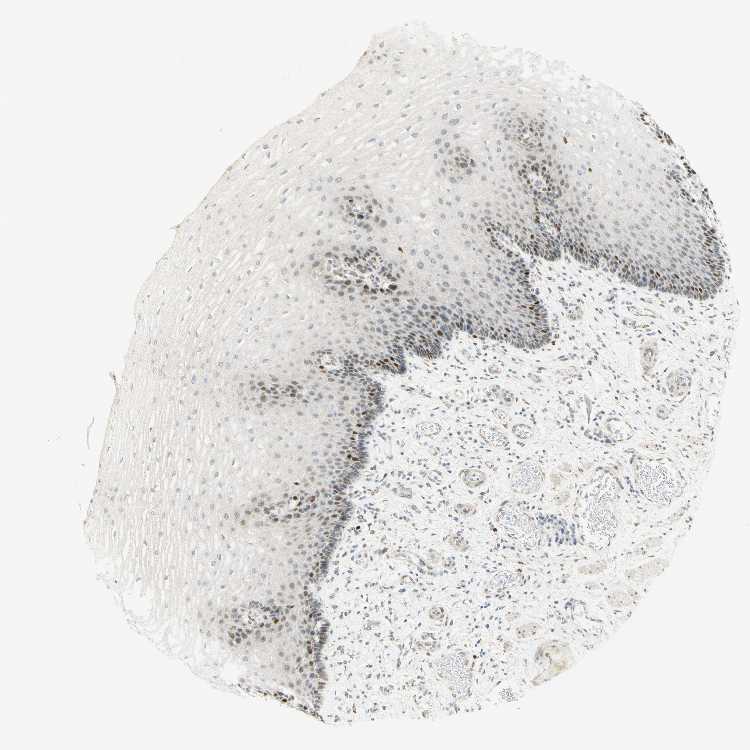

ESOPHAGUS - Antibody stainingi

Antibody staining in the annotated cell types in the current human tissue is reported as not detected, low, medium, or high, based on conventional immunohistochemistry profiling in selected tissues. This score is based on the combination of the staining intensity and fraction of stained cells.

Each image is clickable and will lead to virtual microscopy that enables deeper exploration of all samples and also displays staining intensity scores, fraction scores and subcellular localization as well as patient and tissue information for each sample.

Antibody HPA008003Antibody CAB000329Antibody CAB019308

Squamous epithelial cells HighMediumHigh